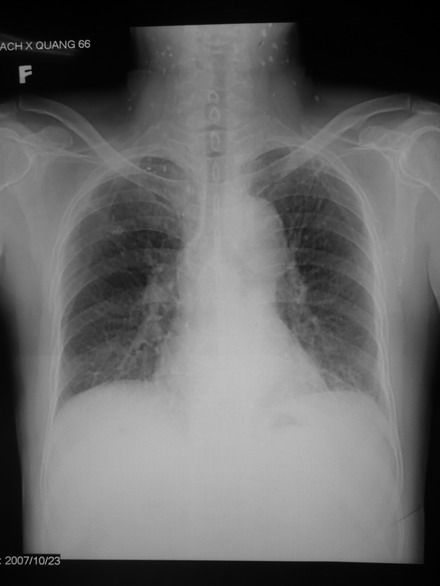

- CT lồng ngực: Phổi phải có tổn thương thành dải xơ co kéo, đỉnh phổi có một số nốt vôi hóa. Hình ảnh dày khu trú màng phổi phải thùy trên.

- Đo chức năng hô hấp: Tiff: 59,8%; FEV1 45,5 %. KL: Rối loạn thông khí tắc nghẽn mức độ nặng.

Triệu chứng hay gặp ở phổi là xơ hóa tiến triển ở phổi, gây khó thở, suy tim và chết trong vòng vài năm nếu không điều trị kịp thời.

Hình ảnh XQ tim phổi thẳng